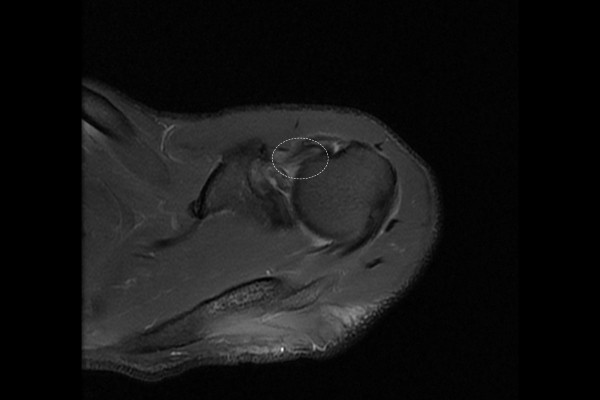

환자분의 어깨 및 이두근 상태를 자세히 파악하기 위해, MRI 촬영을 진행하였습니다. MRI 촬영 결과, 이두근 장두가 관절 내 부분에서 파열이 의심되었고, 어깨 이두근 장두 손상(Biceps long head inj shoulder Lt.)을 진단하였습니다. 이두근 장두건은 어깨 관절 위쪽을 지나며, 팔을 들어 올리거나, 돌리는 동작에 중요한 역할을 하는 만큼, 주로 팔을 자주 사용하는 분들에게 손상 및 파열 증상이 나타납니다.(퇴행성 변화나 교통사고 등 외부의 충격으로도 발생할 수 있습니다.)

환자분께 MRI 사진과 함께 현재 어깨 이두근 상태와 수술적 치료의 필요성을 설명드렸고, 어깨 이두근 장두건 재부착술(Biceps long head tenodesis)을 시행하였습니다.